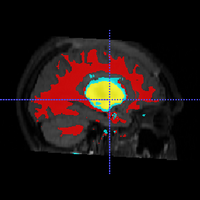

• Segment longitudinal brain MR images with TBI using personalized atlas construction.

• We got two new subjects from UCLA DBP. We processed the data and tested the current algorithm.

• Bo Wang, Marcel Prastawa, Andrei Irimia, Micah C. Chambers, Paul M. Vespa, John D. van Horn, Guido Gerig, A Patient-Specific Segmentation Framework for Longitudinal MR Images of Traumatic Brain Injury, SPIE Medical Imaging 2012.